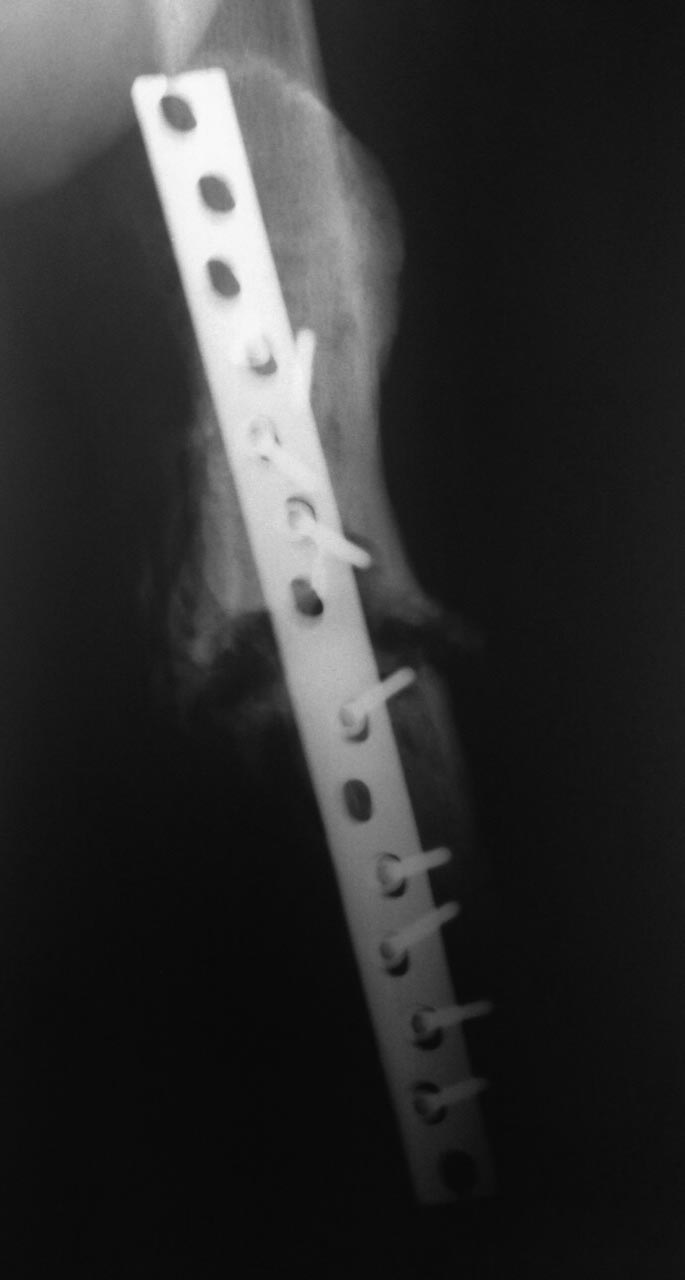

Боковая проекция.